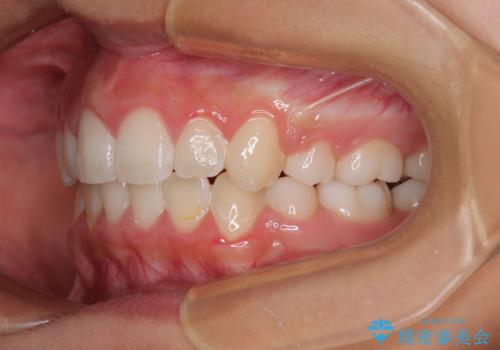

気がつくと唇があいてしまう ワイヤー装置での抜歯矯正

- 口元の突出感で口が閉じにくいとのことで来院された患者様です。

上下左右の第一小臼歯4本を抜歯し、ワイヤー装置での抜歯矯正を行うこととしました。

右側の咬み合わせは、上顎がやや前方位にある状態であったので、通常は補助装置を併用するのですが、高校生ということで補助装置なしで治療を行うこととしました。

口元の突出感が解消され、睡眠時の口呼吸が改善されました。